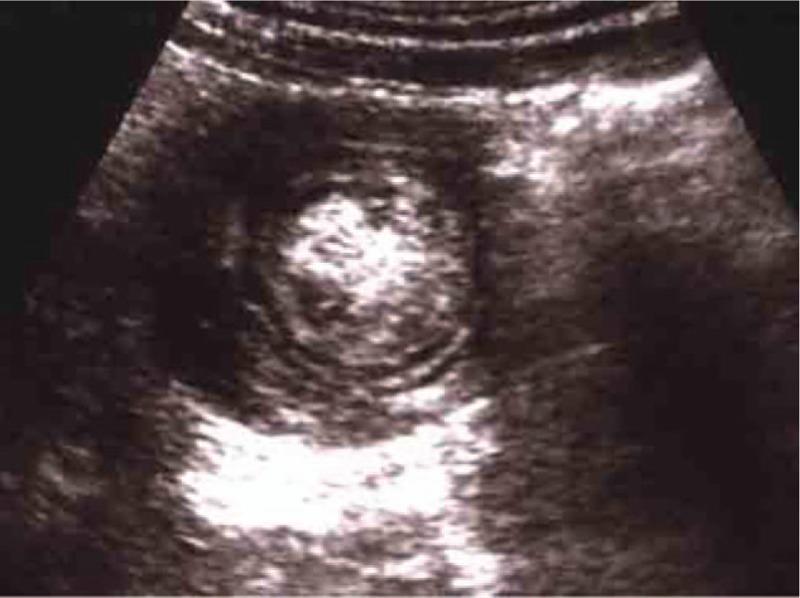

Due to the various presentations of gastrointestinal tract duplications (GTD), diagnosing and management for this disease might be varied and difficult. We intend to improve the experiences for these difficult, in terms of the clinical presentations, diagnostic investigations, management.We reviewed recent literature and retrospectively analyzed 72 pediatric patients with enteric duplication. Diagnosis was confirmed by surgery and pathological examination for imaging characteristics and clinical and pathological features.The ages of patients ranged from one month to 12.5 years. The clinical presentations of the patients included 57 cases with abdominal pain, followed with nausea or vomiting, abdominal distension, etc. All of the patients were diagnosed by ultrasonography, and most of them presented as intra-abdominal cystic masses. Four cases were diagnosed with the cysts other than GTDs, like, mesenteric cyst, chledochal cyst and abscess, and so on. Computed tomography was performed on 65 patients. X-rays and barium meal showed the outline of the cyst structure, with intestinal displacement due to the pressure from the cyst. Among the 72 cases of enteric duplication, 45 were located with ileocecal area, 41 were ileal and 8 were colonic duplications.Enteric duplication is very rare in children and is prone to misdiagnosis. The preoperative diagnosis of enteric duplication can be improved through comprehensive analysis of various imaging exams and closely related clinical presentations.

由于胃肠道重复畸形(GTD)的表现多样,该病的诊断和治疗可能存在差异且具有挑战性。我们旨在从临床表现、诊断检查、治疗等方面改善对这些疑难病症的诊治经验。我们回顾了近期文献,并对72例小儿肠重复畸形患者进行了回顾性分析。通过手术及病理检查,依据影像学特征以及临床和病理特征确诊。患者年龄从1个月至12.5岁不等。患者的临床表现包括57例腹痛,随后伴有恶心或呕吐、腹胀等。所有患者均通过超声检查确诊,大多数表现为腹腔内囊性肿块。4例被诊断为非GTD的囊肿,如肠系膜囊肿、胆总管囊肿和脓肿等。65例患者进行了计算机断层扫描。X线和钡餐显示了囊肿结构的轮廓,由于囊肿的压迫导致肠管移位。在72例肠重复畸形病例中,45例位于回盲部,41例为回肠重复畸形,8例为结肠重复畸形。肠重复畸形在儿童中非常罕见,且容易误诊。通过综合分析各种影像学检查和密切相关的临床表现,可以提高肠重复畸形的术前诊断率。